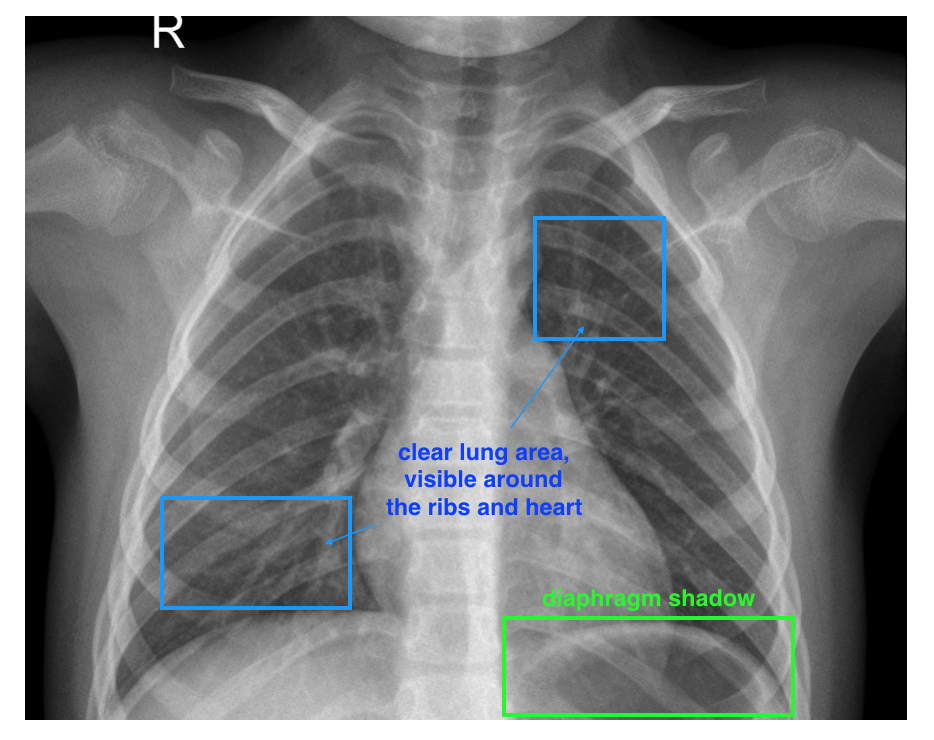

This dataset is a modified version of Kaggle chest x-ray dataset, with most labels removed. Every piece of data is a chest x-ray image. You may see images taken that are slightly different in size and taken under slightly different exposure times. A typical, labeled image is shown below.

A labeled, healthy, chest x-ray image. Pay close attention to the two lungs and diaphragm (below the lungs)

There are a few different visual symptoms that indicate pneumonia. The most important areas to have annotators pay attention to are the lungs and the diaphragm.

- A normal, healthy image will depict clear lungs without any areas of abnormal cloudiness/opacity; there may be structured, web-like vasculature in the lungs but otherwise that area should be clear. In healthy images, you are also more likely to see a diaphragm shadow.

Some characteristics of a healthy image: a clear lung area